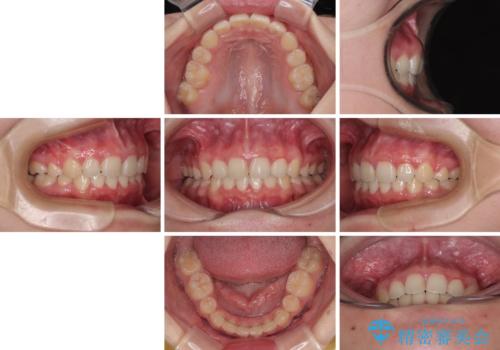

飛び出した口元を改善したい ワイヤー装置による抜歯矯正治療

- 下唇の上に乗っかってしまうくらい前歯が飛び出していることを気にして来院された患者様です。

唇を閉じようとするとオトガイ部に力が入ってしまい、うまく閉じることができない状態であったため、上下左右の第一小臼歯4本を抜歯して、ワイヤー装置にて矯正治療を行うこととしました。

飛び出した前歯はしっかりと引っ込み、横顔の印象が大きく変化しました。